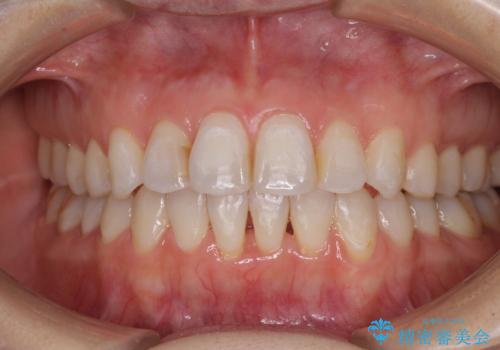

- 11ヶ月

インビザライン適用の歯列であったため、歯と歯の間を削るIPRを用いて改善することとしました。

下顎前歯の叢生が顕著な場合、歯列改善後に歯と歯と歯肉の間にブラックトライアングルという隙間ができてしまいます。

軽減することはできますが、完全に解決することは矯正治療のみでは不可能なため、リスクとして事前に周知しておく必要があります。